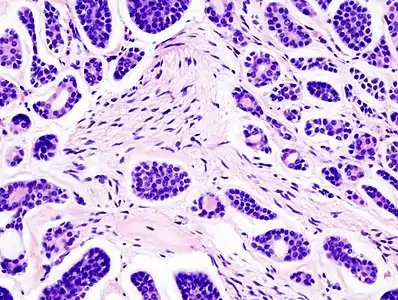

| Micrograph of an adenoid cystic carcinoma of a salivary gland (right of image): Normal serous glands, typical of the parotid gland, are also seen (left of image), H&E stain. | |

Histopathological image of adenoid cystic carcinoma of the salivary gland infiltrating a nerve (center), H&E stain